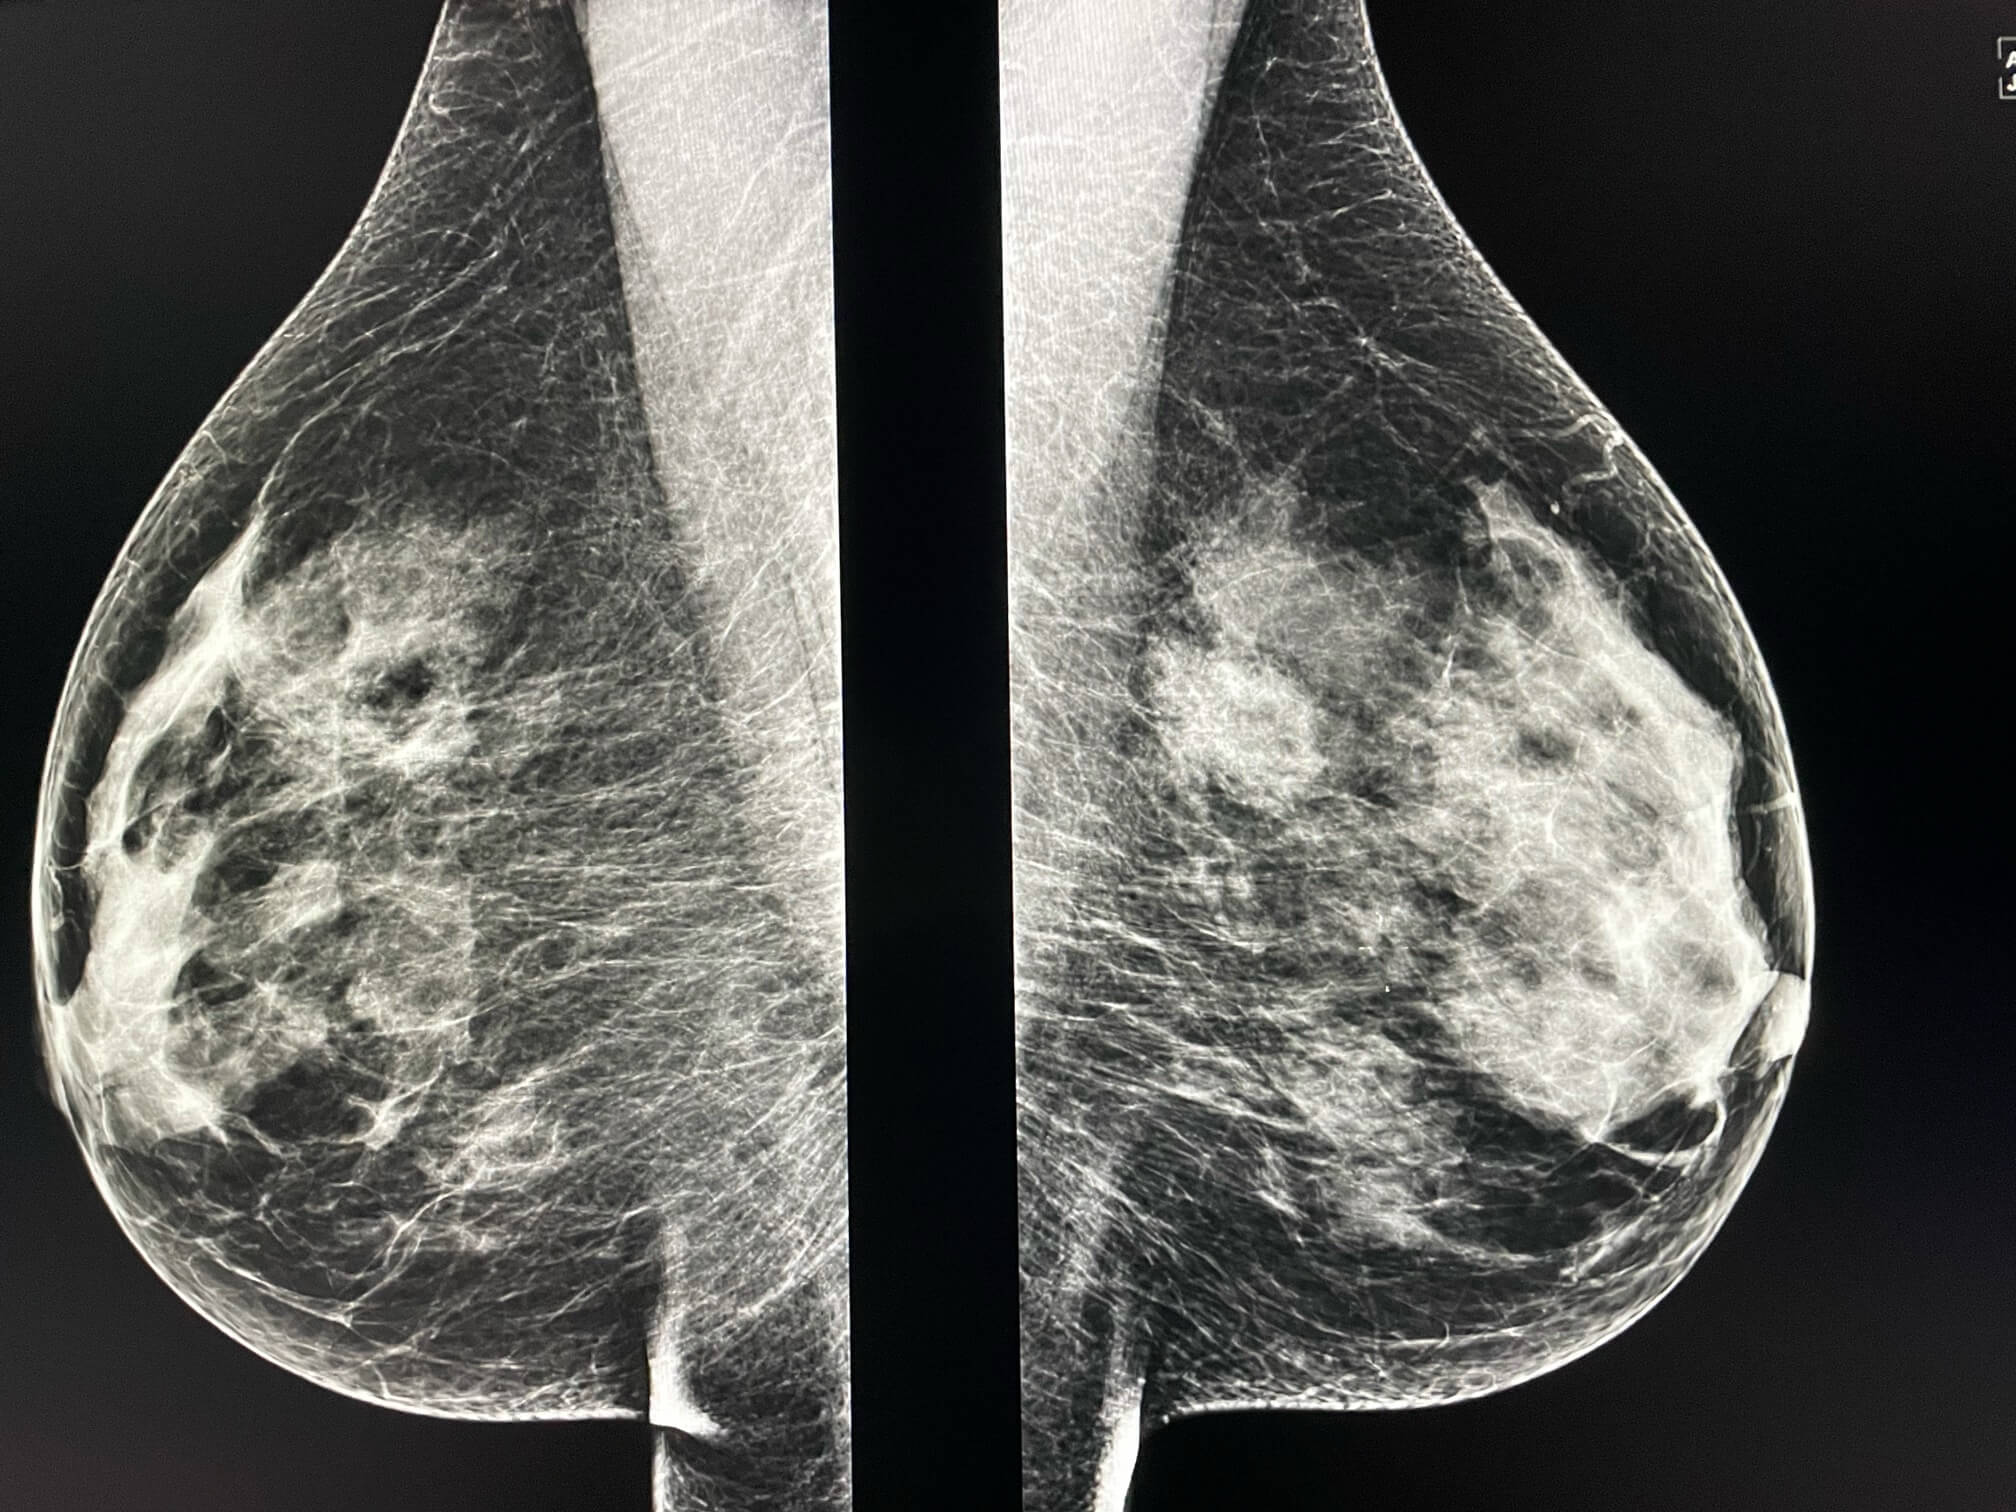

Femme de 57 ans, mammographie de depistage.

MammoScreen™ pointe un foyer de microcalcifications constitué d’une dizaine de microcalcification polymorphes, irrégulières ( drapeau rouge).

Ce foyer n’était pas présent sur la mammographie antérieure.

Une macrobiopsie stéréotaxique du foyer de microcalcification est réalisée: carcinome intra canalaire de grade 2.